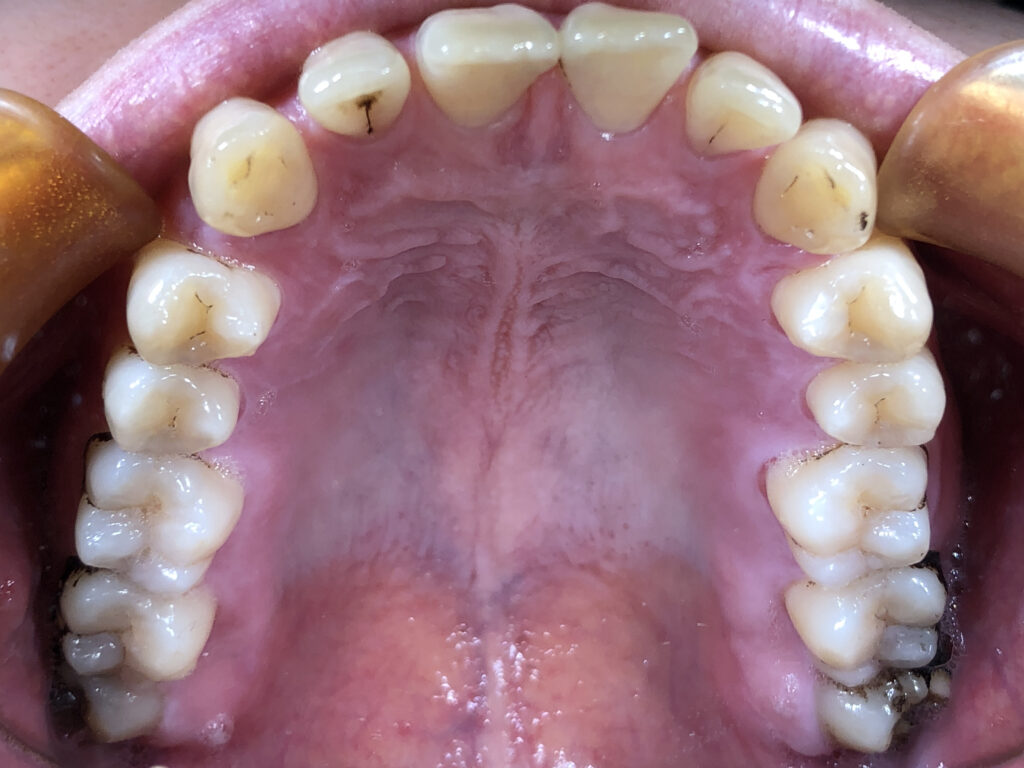

上顎

治療前

治療後

患者様は上下の横の前歯の隙間を気にされており、「できれば完全に隙間を閉じたいが、ある程度改善されればよい」とのご希望で来院された。 インビザライン矯正では、前歯の近接移動を中心に計画し、効率的に隙間を閉鎖するため犬歯・小臼歯にアタッチメントを付与。また、閉鎖後の歯肉退縮やブラックトライアングルを最小限に抑えるため、歯根の平行性を意識して移動を行った。 治療により上下前歯の隙間は良好に閉鎖し、咬合も安定。審美的な改善とともに、発音や清掃性の向上にもつながった。 |